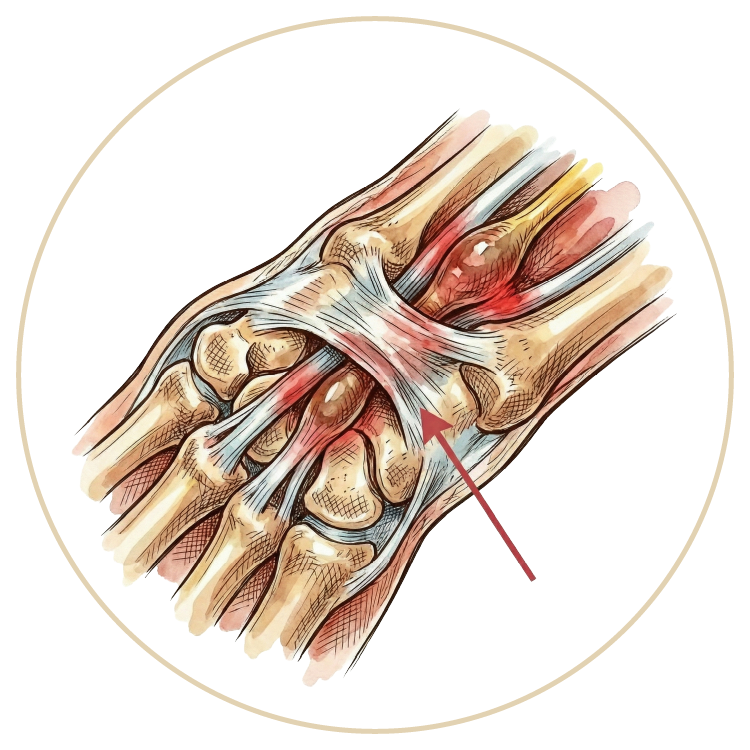

El, Bilek ve Dirsek Hastalıkları

Karpal Tünel Senromu